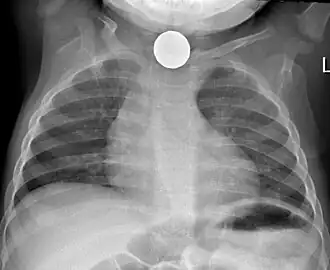

Foreign body aspiration

Foreign body aspiration is a major cause of death in young children due to their underdeveloped swallowing coordination. Young children most commonly ingest toys, coins, or food.[21] On chest x-ray, the most frequent sign is air trapping that can lead to a mediastinal shift. Atelectasis and pneumothorax may also occur in the setting of foreign body aspiration. The diagnosis is made in conjunction with clinical symptoms and confirmed and treated with bronchoscopy.[22]